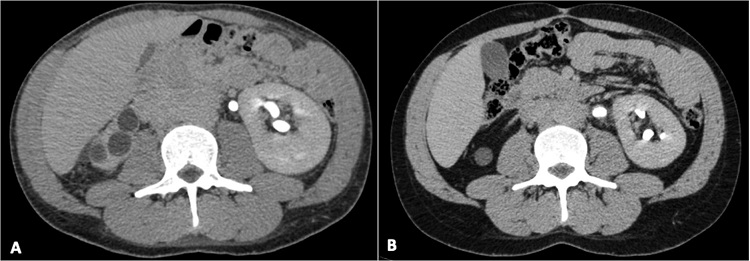

Abdominal computed tomography (CT) showed a large, contrast-enhanced mass (10 x 8 x 4cm) involving the abdominal infrarenal aorta and the iliac arteries and compressing the inferior vena cava with dilated iliac veins and the left ureter (Figure 1A), raising the hypothesis of the lymphoproliferative disease. The liver had normal size but had a heterogeneous attenuation.

The patient was started on 1.0 mg/kg/day of prednisone for 2 weeks and then tapered for 0.6 mg/kg/day for two months, and to 20 mg/day for 3 months, afterward. The outcome was favorable and he gradually recovered his previous health status. The abdominal and lumbar pain ceased in about 3 weeks after starting treatment, his hemoglobin level returned to normal and his inflammatory markers decreased. Five months after initiation of corticotherapy, a new abdominal CT scan was done (Figure 1B), and the initial contrast-enhanced mass had almost disappeared, but it showed an inferior vena cava thrombosis extending to bilateral external iliac veins. He was started on warfarin. The double J ureteral stent was removed, and the patient remains asymptomatic with a good urine output with no renal function impairment. At the closure of this manuscript, he was asymptomatic and taking only 5 mg/day of prednisone.